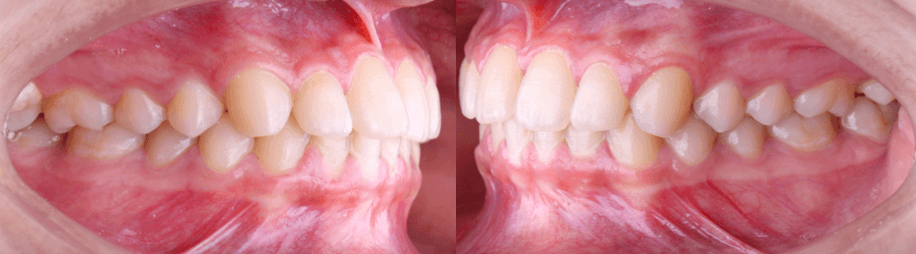

Intraoralmente, la paciente presenta una relación molar y canina clase I bilateral (figura 4), con apiñamiento leve en el sector anterior de ambas arcadas (figura 5). Se observó un overjet de 2 mm y overbite de 3 mm. Los segundos molares superiores se encontraban ligeramente vestibularizados y fuera del arco, configurando una mordida telescópica (figura 6). Esta posición contribuía a la discrepancia oclusal y a la disfunción funcional referida.

Figura 4. Fotografias intraorales derecha e izquierda.